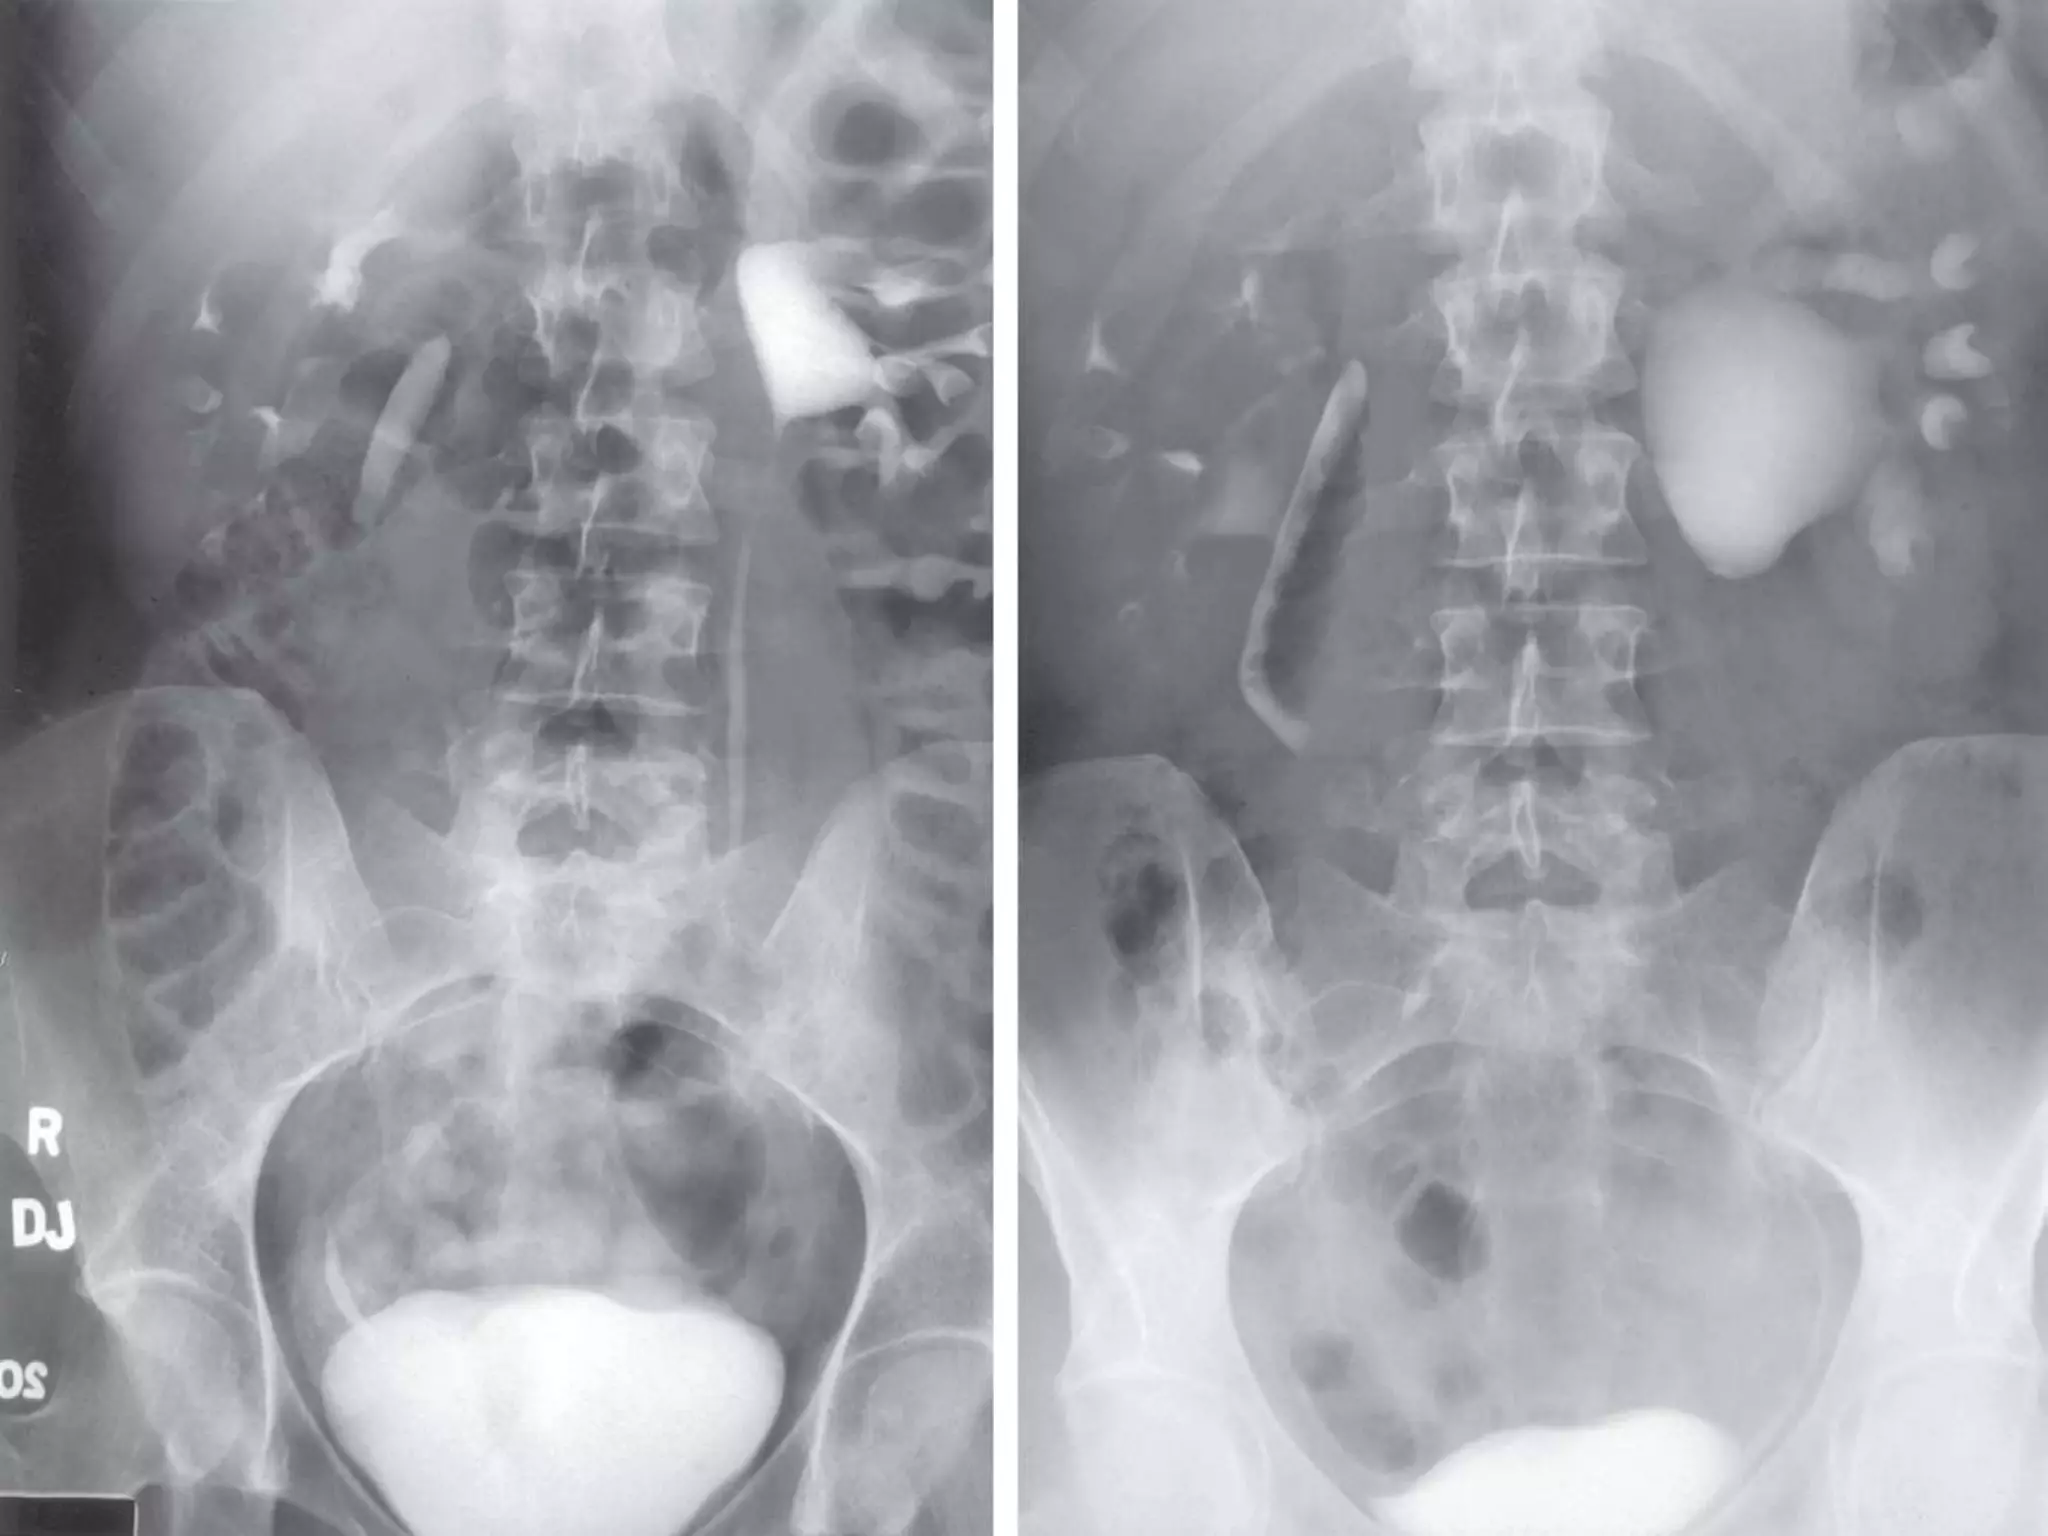

VOIDING CYSTOURETHROGRAM (VCUG)

-It is performed in patients with hydronephrosis to

confirm the presence or absence of VUR of

both the affected and contralateral kidneys.

-10% of patients with UPJ obstruction have

contralateral low-grade vesicoureteral reflux.

-Identification of VUR is important because

children with concurrent VUR and UPJ

obstruction may be at higher risk for severe

infection.

VOIDING CYSTOURETHROGRAM (VCUG) -Itis performed in patients with hydronephrosis to confirm the presence or absence of VUR of both the affected and contralateral kidneys. -10% of patients with UPJ obstruction have contralateral low-grade vesicoureteral reflux. -Identification of VUR is important because children with concurrent VUR and UPJ obstruction may be at higher risk for severe infection.